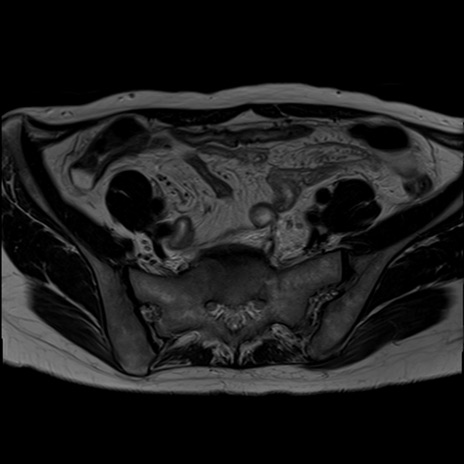

症例39 T2WI(横断像)

MRI(4日後)